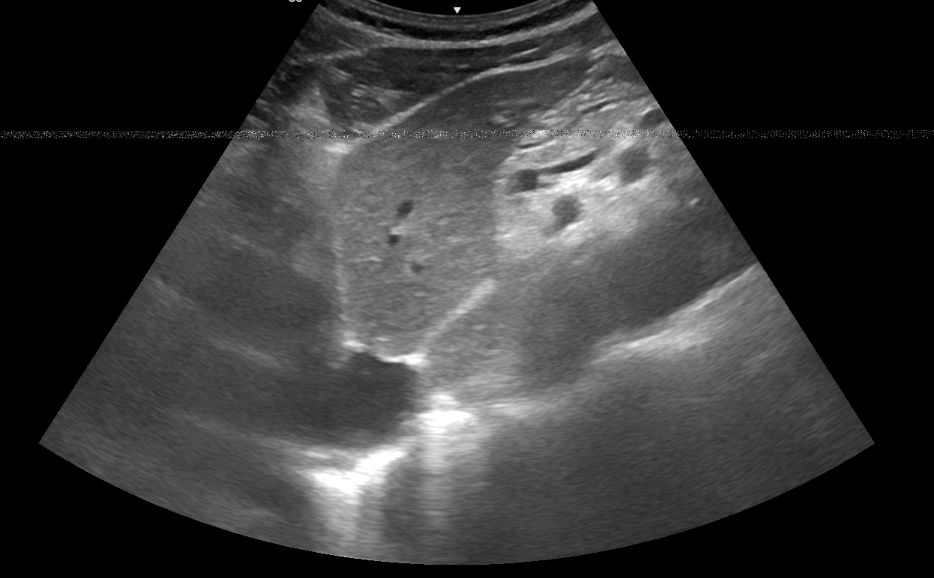

Compensación de Ganancia por Tiempo (TGC)

La compensación de ganancia por tiempo (TGC) ajusta la ganancia de forma independiente a diferentes profundidades, ayudando a mejorar la uniformidad de la imagen al corregir la atenuación del ultrasonido en tejidos más profundos. Esto garantiza una visualización clara tanto de las estructuras superficiales como profundas, optimizando la calidad de la imagen.

Explora más sobre TGC en el simulador interactivo.

TGC en ecografía

Imagenus 6: Ejemplo de ajuste de TGC en ecografía para mejorar la imagen en profundidad.

Simulador de TGC Al pulsar sobre la imagen accederás a un jugable docente.

Simulador de TGC

Figura 6: Simulador interactivo de TGC para ajustar la imagen en función de la profundidad.